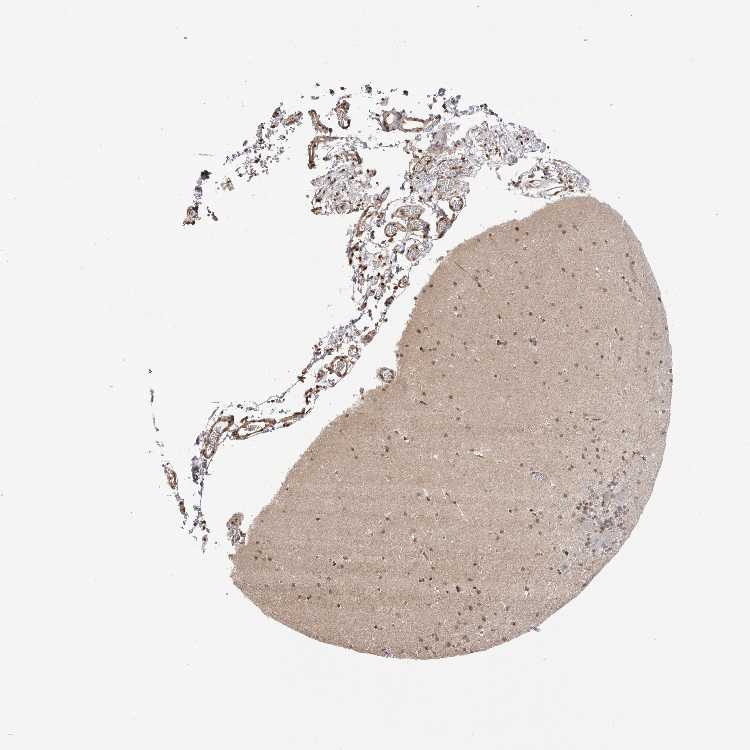

CEREBELLUM - Antibody stainingi

Antibody staining in the annotated cell types in the current human tissue is reported as not detected, low, medium, or high, based on conventional immunohistochemistry profiling in selected tissues. This score is based on the combination of the staining intensity and fraction of stained cells.

Each image is clickable and will lead to virtual microscopy that enables deeper exploration of all samples and also displays staining intensity scores, fraction scores and subcellular localization as well as patient and tissue information for each sample.

Antibody HPA010023Antibody CAB025529

Purkinje cells MediumNot detected

Cells in granular layer Not detectedLow

Cells in molecular layer MediumMedium